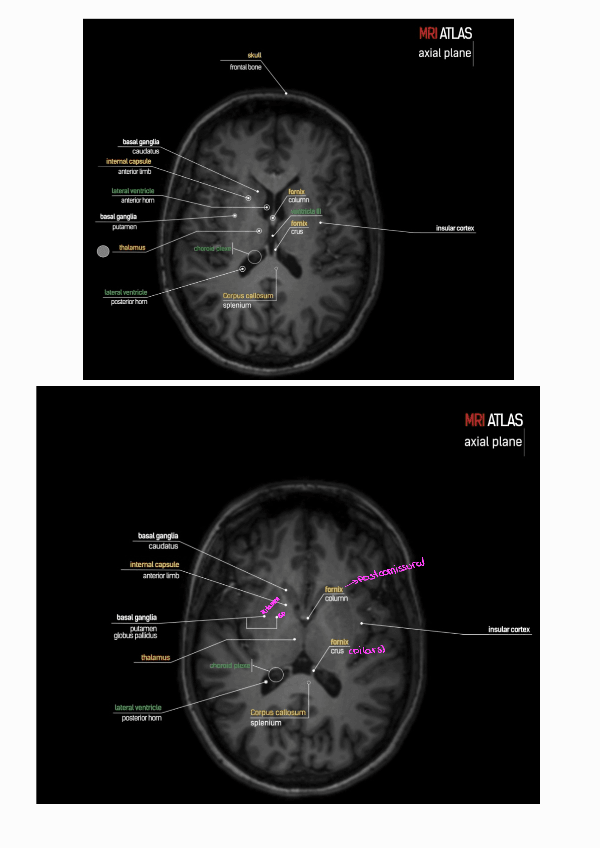

He publicado nuevos practicas de 3º Radiologia General: PRACTICA-3-RADIOLOGIA-1.pdf

3 páginas